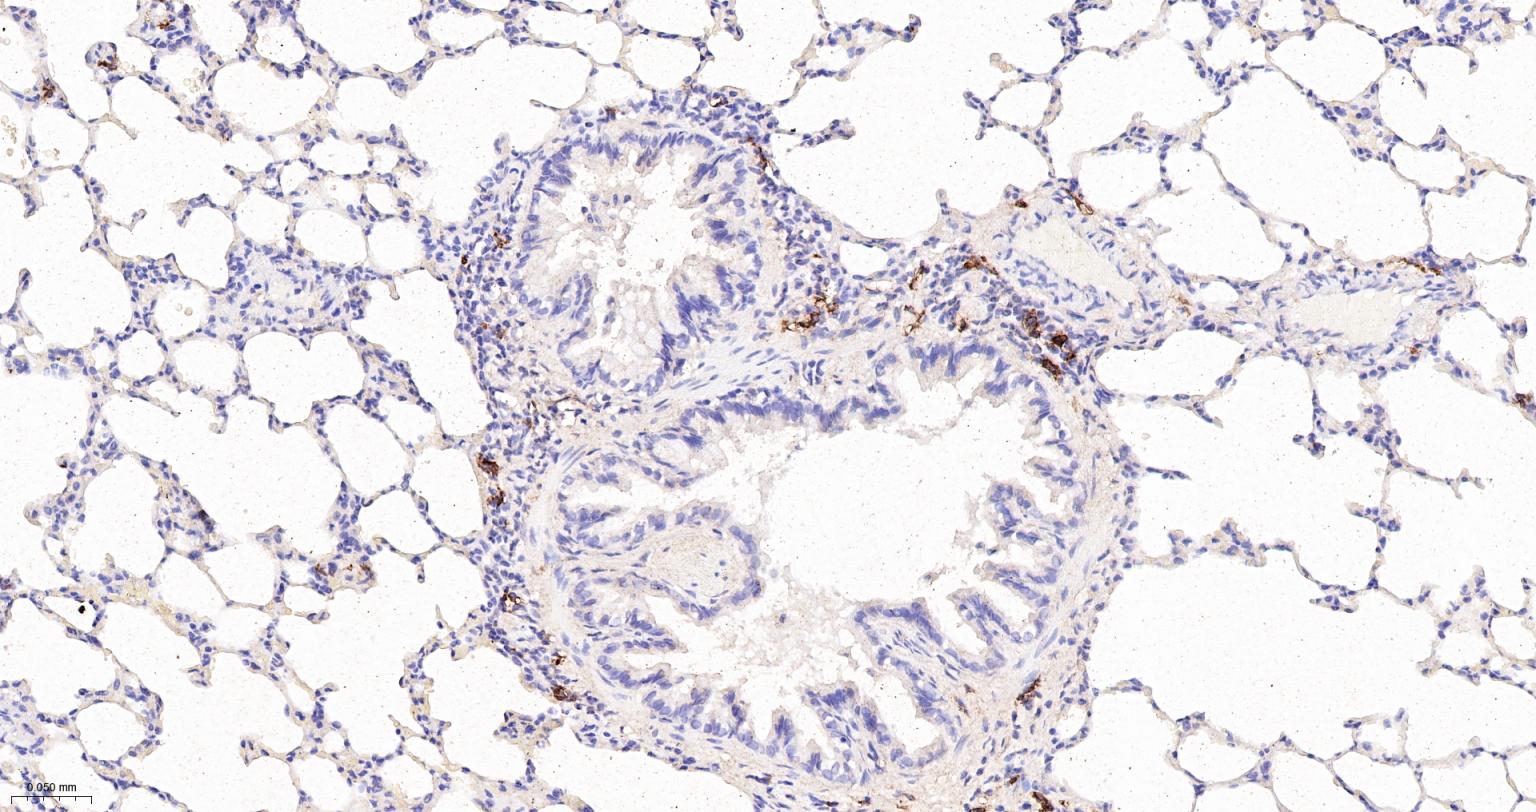

Paraformaldehyde-fixed, paraffin embedded Mouse Lung; Antigen retrieval by boiling in sodium citrate buffer (pH6.0) for 15 min; Antibody incubation with CD163 Monoclonal Antibody, Unconjugated(bsm-54015R) at 1:200 overnight at 4°C, followed by conjugation to the bs-0295G-HRP and DAB (C-0010) staining.